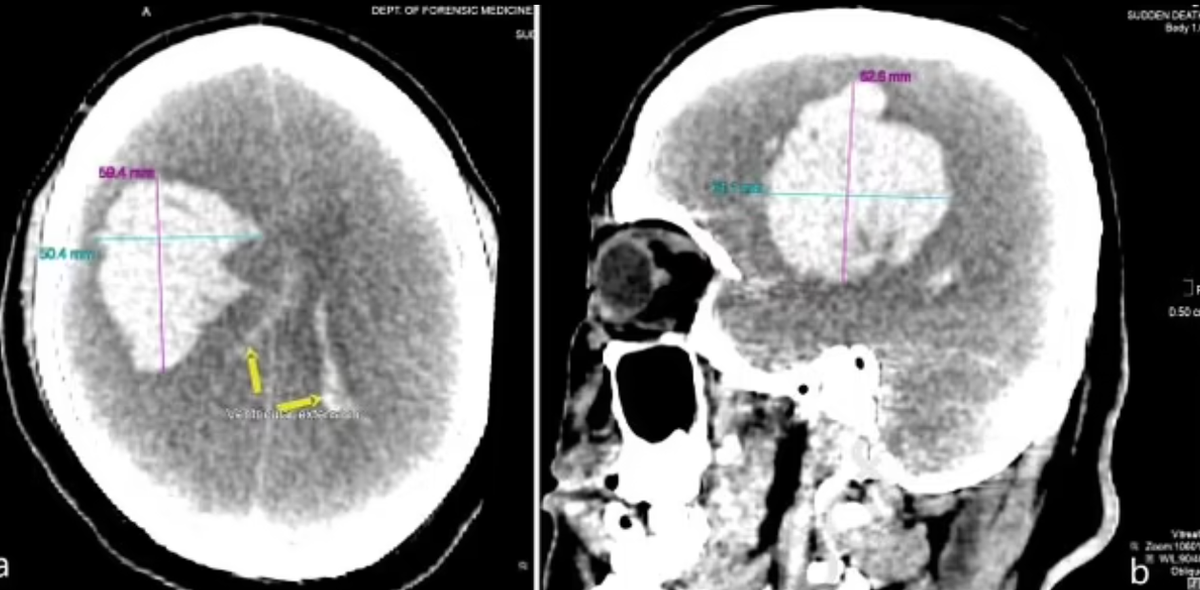

综合上述状况,法医因此推断,男子在过量药物和酒精的影响下,导致严重高血压,并进一步引发中风,最后造成脑血管破裂,同时发现男子脑部有300克血块(图)。